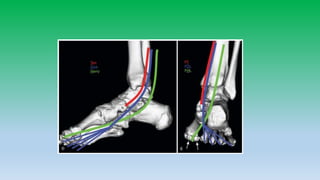

Lateral ankle tendon:

• Peroneus brevis and peroneus longus tendons pass posterior and

inferior to lateral malleolus in the retro-malleolar groove.

• Peroneus brevis is flatter and broader lies anterior to longus, whereas

peroneus longus is posteriolateral and is more rounded. Peroneal

tendons are held inplace by superior retinaculum.

• Split tears are common in brevis.

• Peroneal tendons can sublux or dislocate , whenever there is tear of

superior retinaculum. Diagnosis is made if tendons are located lateral

to distal fibula rather than posterior to it. Hypoplastic retromalleolar

groove can predispose to subluxation.